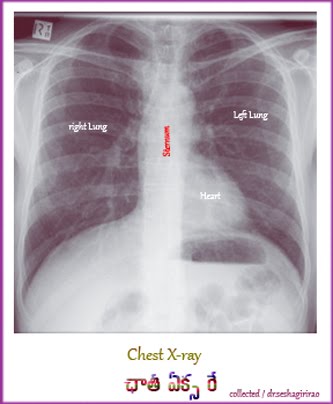

* మన శరీరంలో చాలా రోగాలు ఎక్స్రేల ద్వారా కనిపెట్టవచ్చు. మనం ఎక్కువగా గుండె, ఊపిరితిత్తుల వ్యాధులు, ఎముకలు, జీర్ణకోశ వ్యాధులలో ఎక్స్రేలను వాడుతున్నాం.